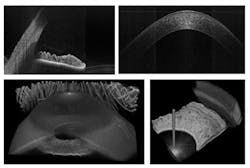

The achievable image quality at multi-megahertz line rates has been investigated in highly scattering tissue using a 1300 nm FDML laser. At line rates up to 5 MHz, good image quality and penetration depth is observed. By applying advanced averaging protocols, the quality can even be further improved (see Fig. 3).

The ultimate OCT imaging speed can be further pushed by applying a multi-beam scan approach, which has produced a 20.8 MHz A-scan rate with good imaging quality (see Fig. 4).8,25 Such high imaging speeds might be required to investigate transient phenomena in 3-D in real time. The goal is “video rate volumetric imaging.” Video-rate volumetric imaging might become a powerful tool for applications ranging from studies of transient phenomena to real-time surgical monitoring and guidance.

The multi-megahertz FDML also enables the rapid acquisition of 3-D data sets of the entire anterior chamber (see Fig. 6). Because the data set is virtually motion artifact-free, absolute measurements of the geometry are possible.